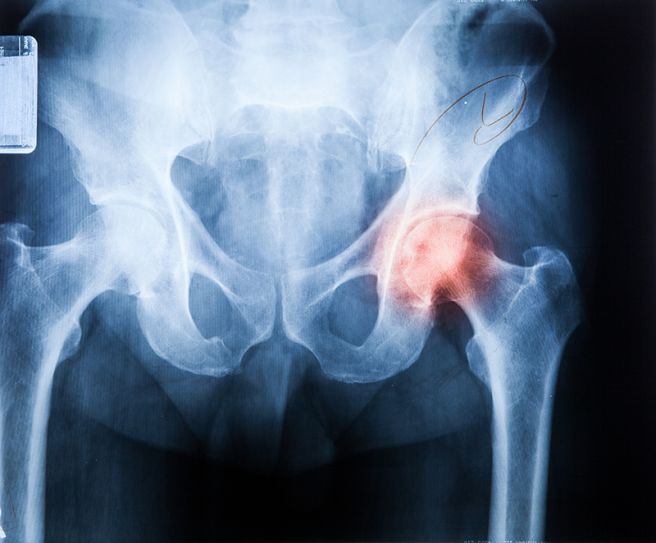

고관절은 인체의 엉덩이 부위에 위치한 관절로 골반과 대퇴골이 연결되는 부위입니다. 보다 정확하게는 골반뼈의 바깥쪽에 위치한 오목한 부분인 비구와, 대퇴골의 상단에 있는 공 모양의 대퇴골두가 만나 형성되는 관절입니다. 공과 소켓 형태로 되어 있어, 다양한 방향의 움직임이 가능하고 체중을 안정적으로 지탱할 수 있도록 만들어져 있습니다.

고관절은 양쪽 엉덩이 부위에 한 쌍으로 존재하며, 골반 양쪽에서 각각 대퇴골과 연결됩니다. 대퇴골두는 골반의 비구 안에 깊숙이 자리잡고 있으며, 관절이 빠지지 않고 안정적으로 유지될 수 있습니다.

고관절 골절은 주로 대퇴경부나 대전자 부위에 발생하며, 뼈의 구조적 손상에 따라 다양한 증상이 나타납니다.

가장 흔한 증상은 극심한 통증으로 보통 넘어지거나 외상을 입은 직후 고관절 부위에 날카롭고 깊은 통증이 발생합니다. 통증은 움직이거나 다리를 들어올리려 할 때 더욱 심해지며, 골절이 심한 경우에는 누워 있는 상태에서도 통증이 지속됩니다.

골절이 발생한 쪽 다리는 반대쪽보다 짧아 보이거나 바깥쪽으로 돌아가 있는 경우가 많고, 특히 대퇴경부 골절에서는 다리의 외회전 변형이 뚜렷하게 나타납니다.